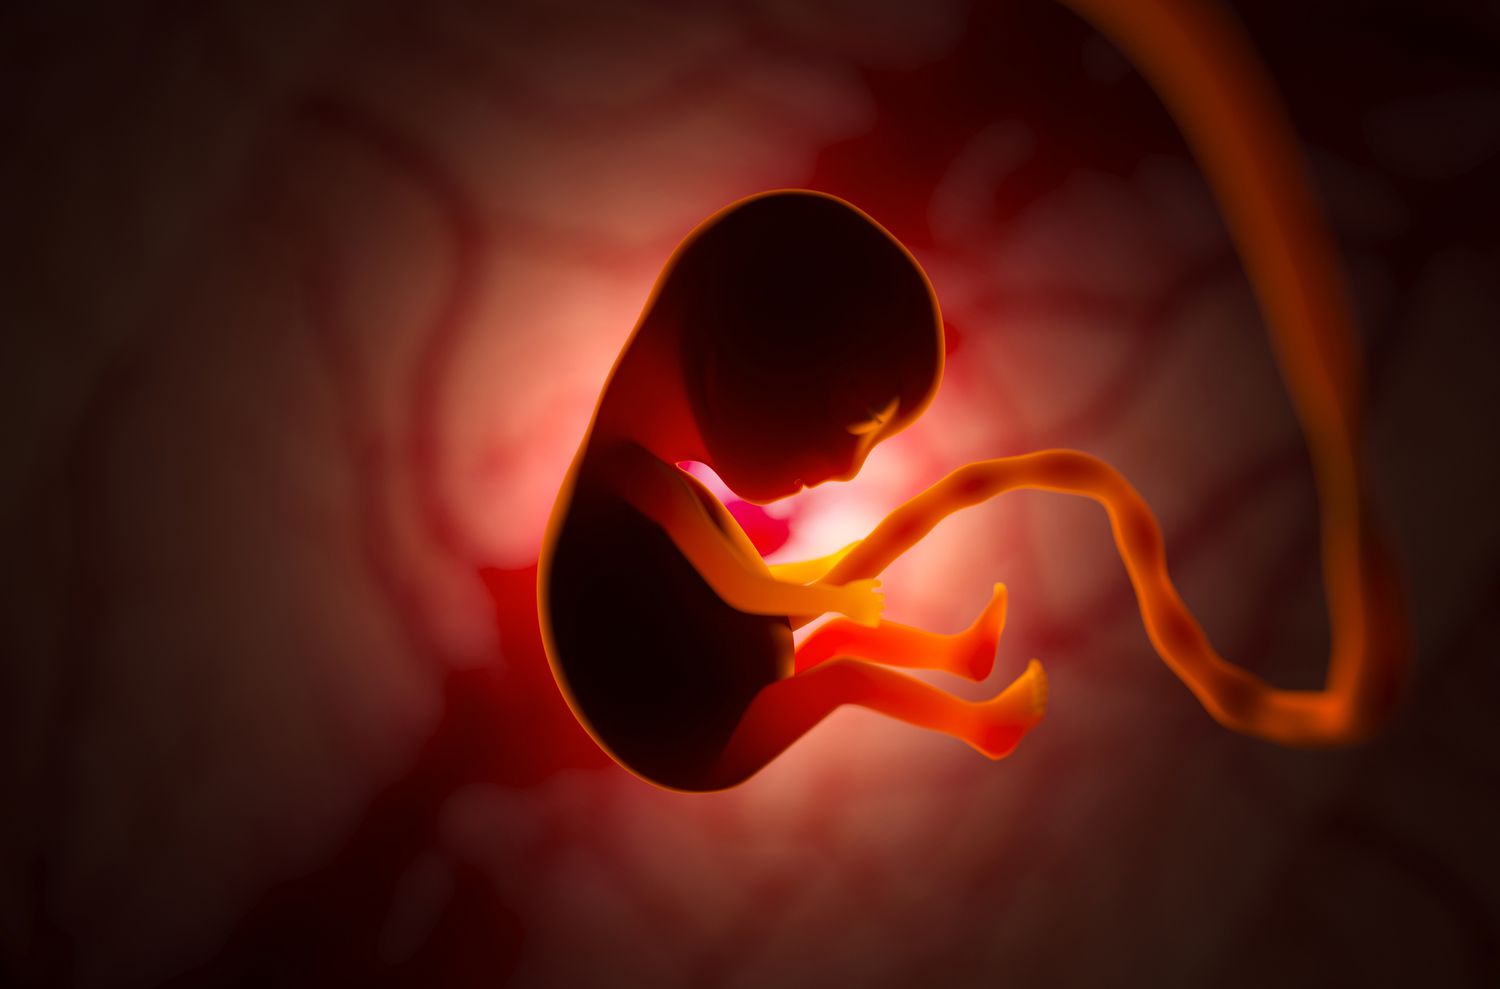

Rising temperatures driven by climate breakdown are causing distress to the foetuses of pregnant farmers, who are among the worst affected by global heating.

A study revealed that the foetuses of women working in fields in The Gambia showed concerning rises in heart rates and reductions in the blood flow to the placenta as conditions became hotter. The women, who do much of the agricultural labour and work throughout pregnancy, told the scientists that temperatures had noticeably increased in the past decade.

There is already strong evidence that extreme heat leads to increases in stillbirths, premature births and low birth weights but this data is from rich, temperate countries. The new study for the first time focuses on subsistence farmers in a tropical country, where increasing extreme heat is a serious concern.

The research is the first step to understanding why foetuses suffer when expectant mothers are stressed by heat. Possible reasons include sweating that leads to dehydration and the diversion of blood and oxygen from the placenta to the mother’s skin to cool the body. The scientists aim to provide evidence for measures to protect expectant mothers and foetuses, such as growing trees to shade women as well as crops.

The scientists also measured humidity, the women’s temperature and the heart rate of expectant mothers and foetuses. The researchers found that when the woman’s body temperature and heart rate rose by one category in a heat strain index, the risk of foetal distress rose by 20 per cent. Foetal distress was indicated by a heart rate over 160 beats per minute, or reduced blood flow to the placenta, as measured by an ultrasound scan.

The team also found that when a measure of heat stress rose by 1C, the risk of foetal distress rose by 17 per cent. It rose by 12 per cent even when the rise in the woman’s temperature and heart rate was accounted for, indicating other factors affecting the foetus. These may include dehydration, low placental blood flow or heat-related inflammation.